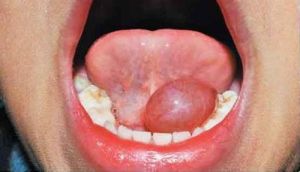

主要是由於舌下腺或頜下腺的導管被阻塞,或者在導管破裂後分泌物外滲形成的囊腫。原因有損傷,涎腺結石、口底部的炎症刺激等。囊腫位於口底,顏色淡藍,常見為1cm直徑的囊腫,但也有腫大明顯的囊腫。舌下囊腫治療可選用CO2雷射及Nd:YAG雷射。治療的關鍵在於徹底處理囊壁,如與涎腺相關一併摘除。手術的複雜性視囊腫大小各異,1cm直徑以下,在局部麻醉後,用雷射刀切開最薄弱處囊壁,排盡腔內物後再用雷射照射內壁。如腔徑較大,直接縫合1~2針。注意,在排出腔內物照射囊壁時要徹底、均勻,但無黑色炭化組織。照射以內壁組織凝固而無再分泌功能即止。

1.位於舌系帶兩側,長大時可超越中線,呈半透明淺藍色膨大。